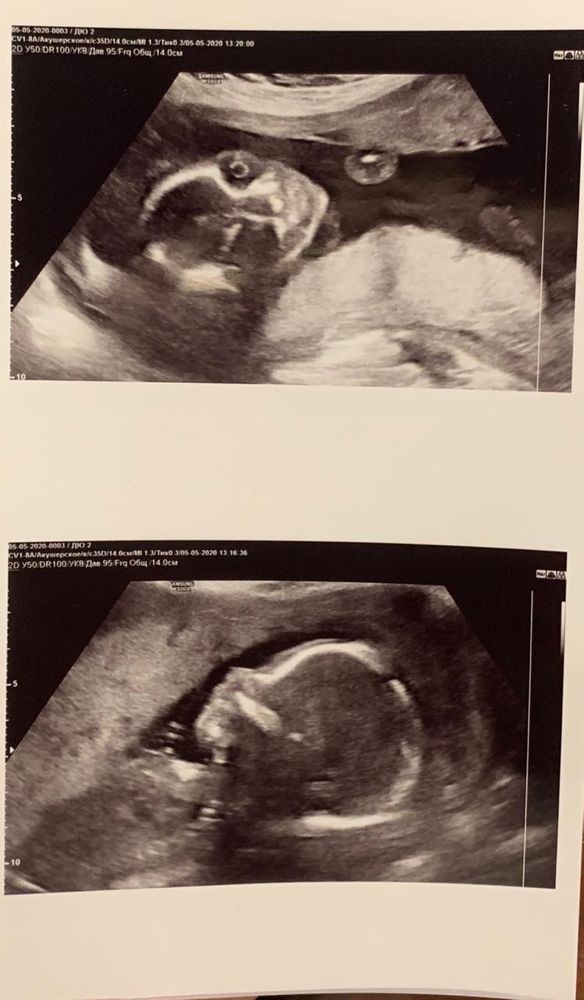

Моя многоплодная беременность от планирования до 36 недель